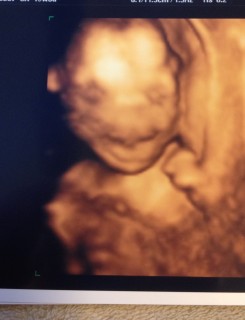

順調に育ってます((´∀`))胎動も、ますます激しくなりました! 今日は、バッチリカメラ目線での最強スマイル(笑)